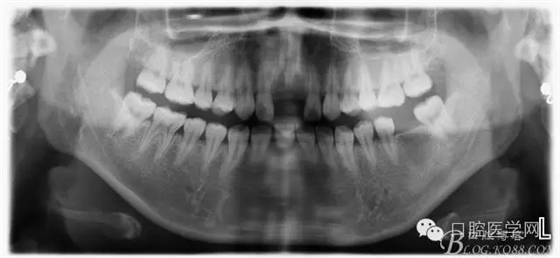

檢查:11.21缺失,笑線高,牙齦較薄,齦乳頭地坪,牙槽骨較飽滿;12.22隱裂,冷熱(一),叩診(一)

術(shù)前:該患者因曾受過外傷,造成兩顆中切齒缺失,來院診治。